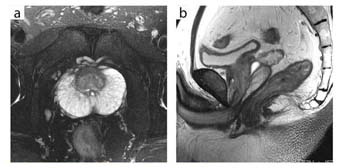

● 骨盤領域(前立腺)への臨床応用

谷本:前立腺は,1.5Tでもそれなりに高画質が得られますが,3Tでうまく撮れたときの美しさにはかないません。例えば,以前撮像した例では,前立腺外腺の導管構築1本1本が鮮明に描出され,直腸内コイルを用いた高分解能MRI以上のきわめて高画質が得られました。ただ,やはり直腸にガスが大量にあるような例では,少しアーチファクトが出ることがあります。そのため,現状では前処置は行っていませんが,将来的には,最初の位置決めスキャンで直腸内に大量のガスが確認された場合は,前処置を行うことも検討するかもしれません。

また当院では,3TではLAVA-FLEXを用いて前立腺のダイナミックMRIを行っています。拡散強調画像を撮像する際のb値は1000と1500で1.5Tと同じですが,S/Nは大幅に向上しています。

当院では精検前のスクリーニングをMRIで行う件数が増えていますので,3T導入の意義は大きいと思います。

![]() 図3 前立腺(32chボディアレイコイル) a:FSE T2WI(脂肪抑制画像),FOV 18cm,スライス厚 4mm,3分34秒 b:FSE T2WI,FOV 18cm,スライス厚 4mm,3分34秒 |